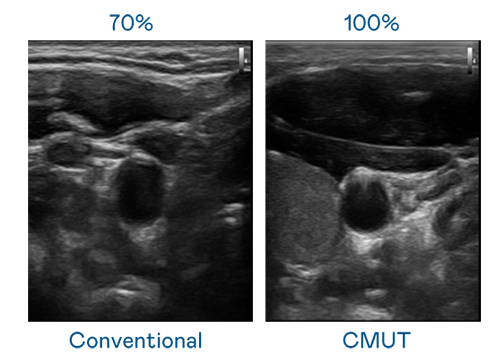

CMUT 技术是一种用电容式微机电元件来产生超音波讯号的技术。与传统 PZT 压电式技术相比,CMUT 频宽增加 30%,更宽频的超音波讯号让影像解析度大幅提升,是实现高影像品质医疗超音波扫描、促进精准医疗发展的关键技术。

大频宽带来超清晰影像

超音波影像的解析度高低,首先取决于探头能发出的讯号频宽。bifa必发 CMUT 可提供高清晰的超音波讯号,提供高频宽、高灵敏度、影像纹理细节更高的超音波影像,协助医护人员缩短影像判读时间及利用精准的医疗影像进行诊断。